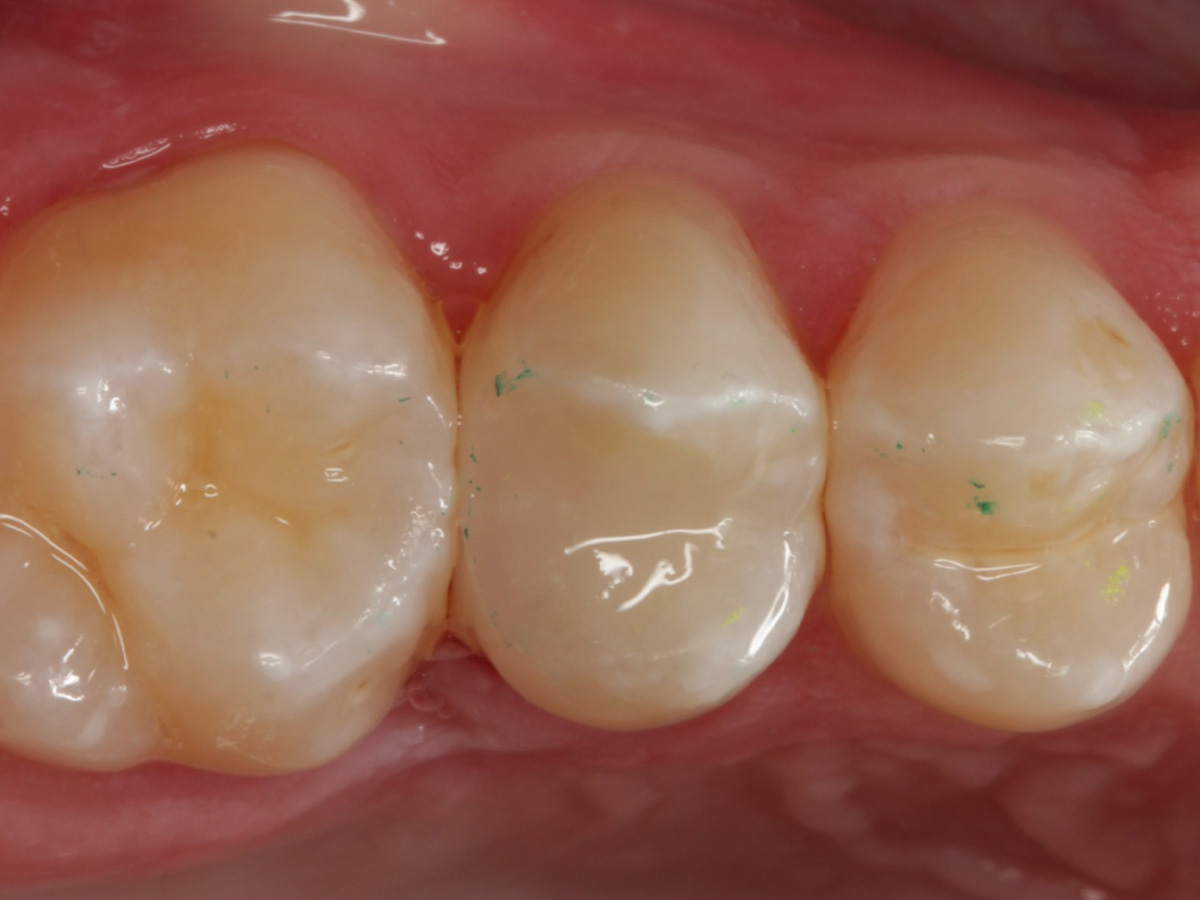

Abbildung 28

Kompositrestauration nach „Schachtverschluß“; keine Krone geplant